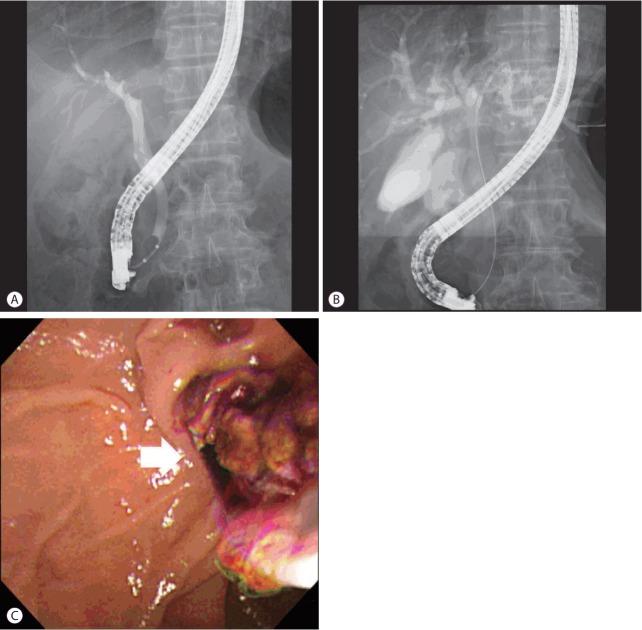

Combined hepatocellular-cholangiocarcinoma (HCC-CC) with bile duct invasion (BDI) is rare. In unresectable cases, biliary stent placement and photodynamic therapy (PDT) are used for resolving obstructive jaundice. However, stent occlusion remains problematic, and PDT is expensive and time-consuming. Intraductal radiofrequency ablation (RFA) is an emerging procedure for palliation in these patients. It has potential benefits including less expense, lower rates of severe complication, longer maintenance of ductal patency, and easier technique compared with PDT or stenting alone. We report a 67-year-old man who underwent repeated intraductal RFA for HCC-CC and HCC with BDI, for whom bile duct patency was maintained without additional biliary procedures.